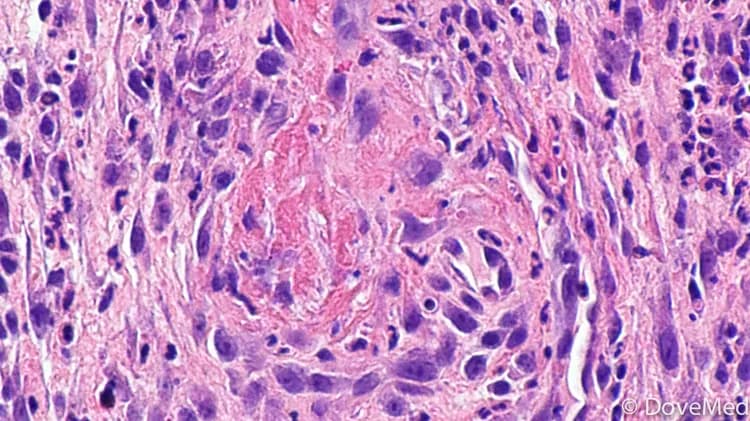

Traumatic Ulcerative Granuloma with Stromal Eosinophilia

A tissue biopsy is the most definitive diagnostic tool to establish Traumatic Ulcerative Granuloma with Stromal Eosinophilia. In this procedure, the physician removes a sample of the oral cavity tissue and sends it to the laboratory for a histopathological examination. The pathologist examines the biopsy under a microscope. The pathologist arrives at a definitive diagnosis after a thorough evaluation of the clinical and microscopic findings, as well as by correlating the results of special studies on tissues (if required).

Tissue biopsy: The biopsy may identify inflammation of the oral tissue that extends into deep tissue. The inflammatory cells are mixed which includes abundant eosinophils, lymphocytes, or histiocytes. Sometimes, atypical histiocytic granuloma (a collection of localized inflammatory cells) may be seen.